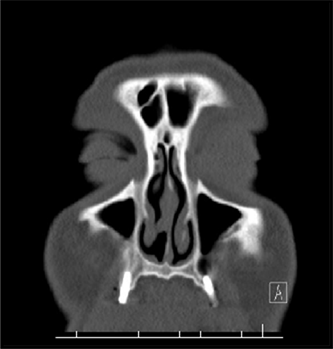

A 66-year-old male who is a known case of nasal hemangiopericytoma that was excised 12 years ago, and who missed regular follow-ups, presented with unilateral nasal bleeding for a couple of weeks. The bleeding was on the right side which was the previously operated side. Nasal examination showed a tan-colored swelling in the middle part of nasal septum (Figure 1). Paranasal sinuses CT scan was ordered. It showed a small well-defined mass in the right side of nasal septum around 1 × 1 cm, not extending into other regions of nasal cavity or paranasal sinuses (Figure 2). The lesion was completely excised by endoscopic surgery. Pathological examination of the lesion showed spindle cells surrounding dilated vessels suggestive of hemangiopericytoma. The patient was followed up for 1 year after the surgery and no recurrence was found. Given the nature of his tumor and its tendency to recur, he was advised for a lifelong follow-up.

Figure 2. Coronal cut of paranasal sinuses showing the lesion arising from the right nasal septum.

Radiological imaging of paranasal sinuses can show the lesion. It appears as a unilateral soft tissue density that enhances with intravenous contrast on CT scan [1] [5] [7]. MRI would show an isointense lesion on T1and an iso- or hypo-intense lesion on T2 that enhances with gadolinium [1] [5].